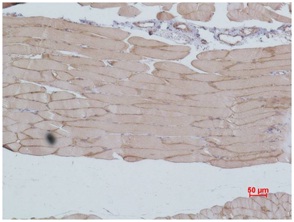

Immunohistochemical analysis of paraffin-embedded Mouse Skeletal MuscleTissue using eEF1A2(BE3363)Rabbit pAb diluted at 1:500.